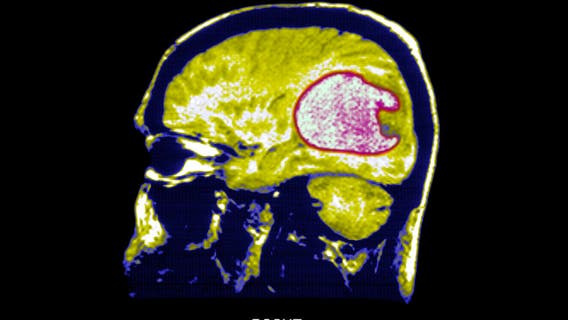

Scientists use new strategy to successfully shrink tumors in early brain cancer trials

Researchers converted immune cells from patients into "living drugs" with the ability to recognize and combat glioblastoma, a form of brain cancer.

Tapeworm larvae found in man’s brain after he complained of migraines

The patient admitted to doctors that he frequently ate undercooked bacon for most of his life.